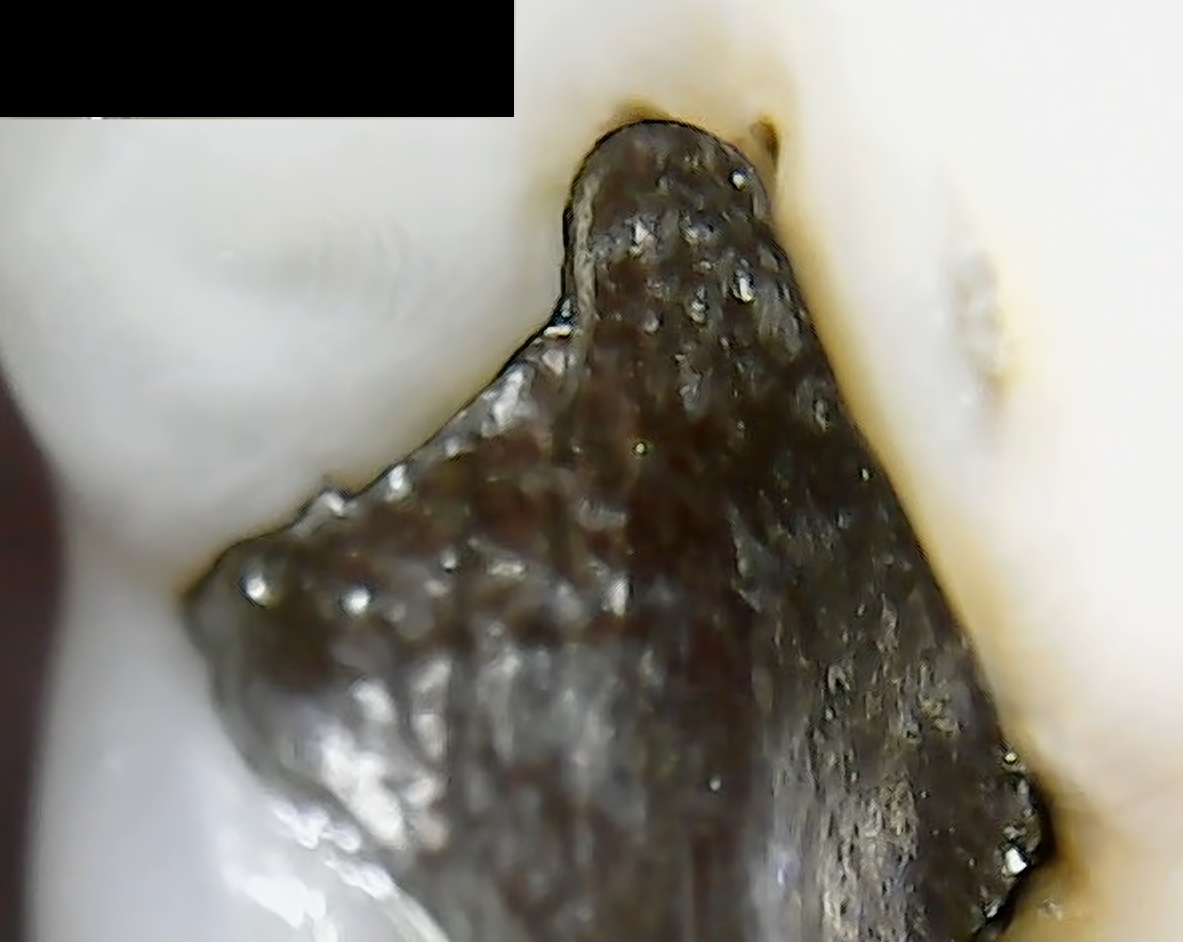

Zu meinen über 20 Jahre alten Amalgam Füllungen würde ich gerne eine weitere Meinung einholen. Es geht um die Backenzähne Nr 36 und Nr 46.

Mittels Mikroskop habe ich folgende Aufnahmen gemacht:

Sind die wirklich noch voll okay?